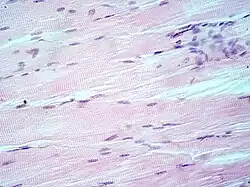

- Músculo cardíaco

Al igual que el músculo esquelético, el músculo cardíaco también es un músculo con estriaciones debido a la presencia de retículo sarcoplásmico y miofibrillas. Inicialmente los investigadores consideraban que la fibra muscular cardíaca era un sincitio como la fibra esquelética. Sin embargo, con el desarrollo de la microscopía electrónica pudo comprobarse que no es un auténtico sincitio anatómico,[30] porque cada fibra miocárdica se encuentra separada de las vecinas por sus respectivos sarcolemas en la zona lateral, que se continúan con los discos intercalares en el extremo de cada fibra.[28]

Estos discos tienen uniones en hendidura, con conductancias muy elevadas,[28] que conectan los citoplasmas de células vecinas lo que lleva a que cuando reciben un potencial de acción se produzca una onda de despolarización —precediendo a la contracción de las aurículas y de los ventrículos— sin que exista un neurotransmisor que desencadene la respuesta,[31] por lo que, si bien el músculo cardíaco no es un sincitio anatómico, se comporta como un sincitio funcional. Los discos intercalares además podrían influir en la cohesión del tejido cardíaco durante la contracción.[30] En el músculo cardíaco, el proceso de formación de las células del tejido es similar al de D. melanogaster —por división, no fusión—, finalizando con la expresión de miogenina, una proteína que comienza el proceso para que se produzca la diferenciación final de la célula muscular.[10]